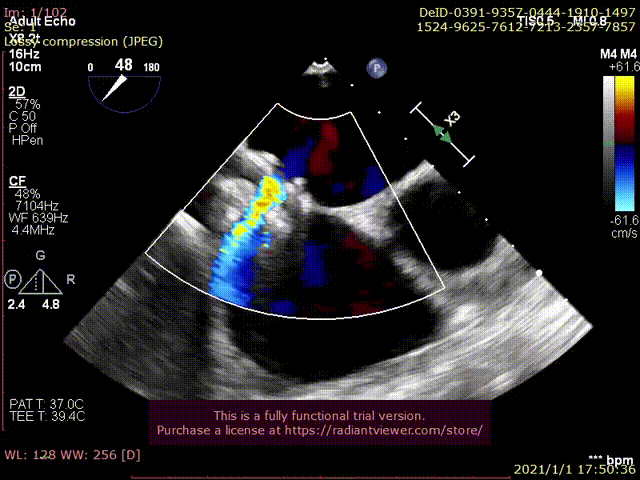

与基线访视水平相比,术后1个月随访时患者的活动耐量显著改善,患者NYHA II级降低至NYHA I级,堪萨斯心肌病问卷评分从57分升高至82分,NT-proBNP从基线时2461pg/ml降低至558pg/m,六分钟步行距离从448米升高至585米。从超声心动图指标观察到患者基线时左心室射血分数为24%,1个月随访时为44%。平均左室收缩末期内径为60 mm,1个月随访时为50mm。平均左室舒张末期内径为68mm,1个月随访时为63mm。肺动脉收缩压26mmHg,1个月随访时为23mmHg。超声可见心房左向右稳定的分流血流信号,缓解左房压。分流孔径最大直径和最小直径分别是4.2mm和3mm,分流孔径保持良好。结果可见SIRIUS AFR心房分流器系统植入后患者的前期左心血流动力学状态有所改善。

经胸超声可见分流器形态良好,无血栓

经胸超声可见左向右分流束